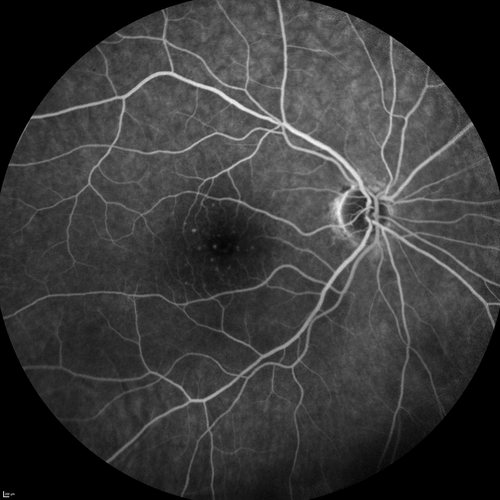

Central Retinal Artery Occlusion with Cilioretinal Sparing - Acute

77-year-old man was doing fine until midnight of last night when he noticed sudden severe vision loss in the left eye. VISUAL ACUITY: OD 20/20, OS 2/200.